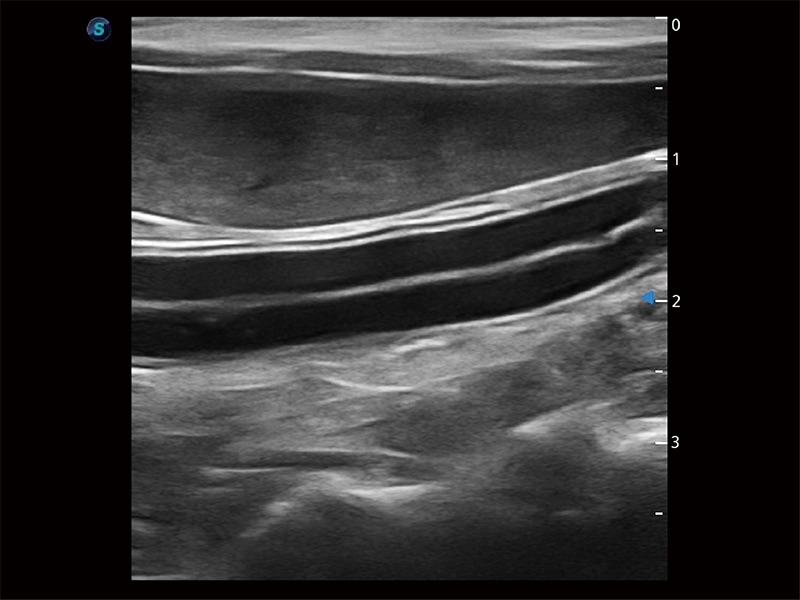

(猫)二尖瓣M型

优异的基础图像

ProPet 80 全新的动物超声智能软件和丰富的探头群,为动物医生提供了高清晰度和精细分辨率的图像,无论在宠物、马科、畜牧还是实验室动物等应用中都可以轻松应对,为您的日常工作带来满意的体验。